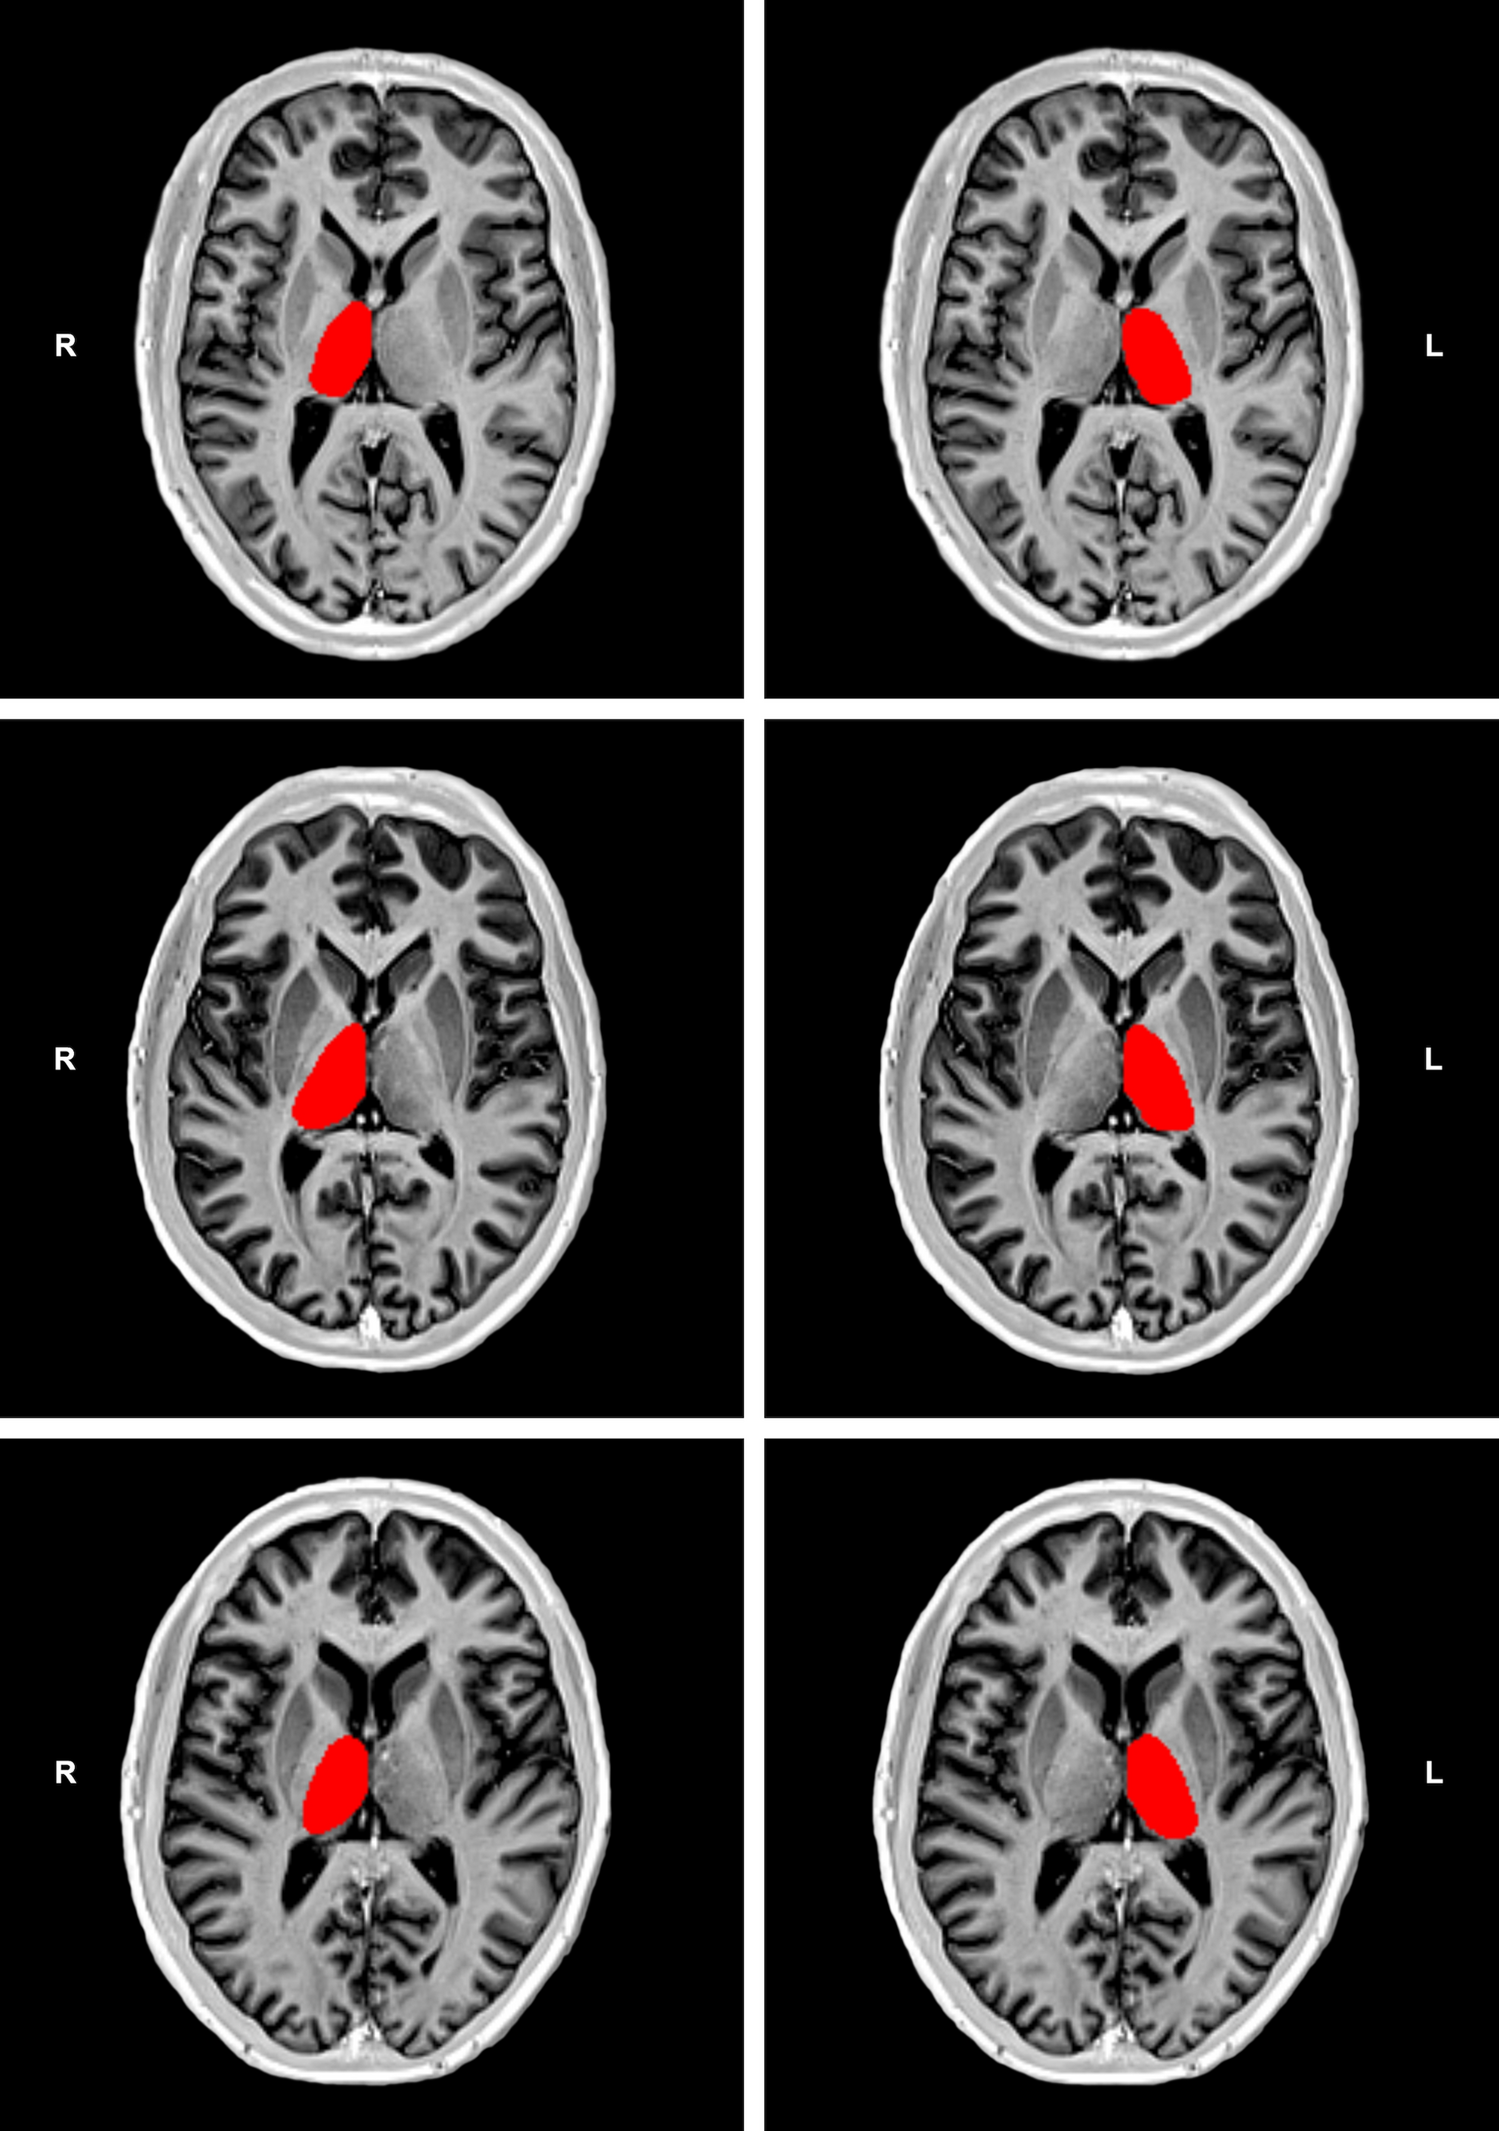

Figure 1

From: Thalamic volumetric abnormalities in type 1 diabetes mellitus and ‘peripheral’ neuropathy

Examples of thalamic segmentation on bias corrected inversion recovery (IR) turbo spin echo (TSE) T1-weighted images (T1-WI) from one patient with nonpainful diabetic peripheral neuropathy (DPN) in the top row and one patient with painful DPN in the middle row. In the bottom row, an example of a similar segmentation procedure on a 46-year-old healthy subject is shown. This example is presented for visualization purposes only, and was randomly selected from a sample of a previous study using similar IR TSE T1-WI to segment deep gray matter structures11. Please note the apparent reduction of thalamic volume (especially the thinner cross-sectional thalamic distance) in the patient with nonpainful DPN, especially in the right thalamus, relative to the other examples.